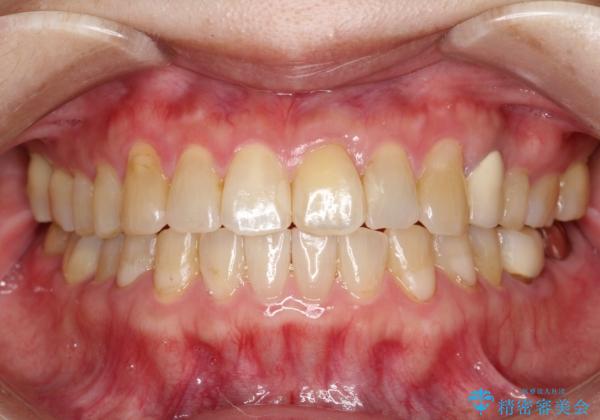

- 前歯のガタガタを主訴に来院されました。

上の歯の前突も気になってたため、奥歯の遠心移動も行いながらインビザラインにて治療を行いました。

前歯も下がり満足していただきました。

今回は奥歯の遠心移動とIPRを行って配列しています。